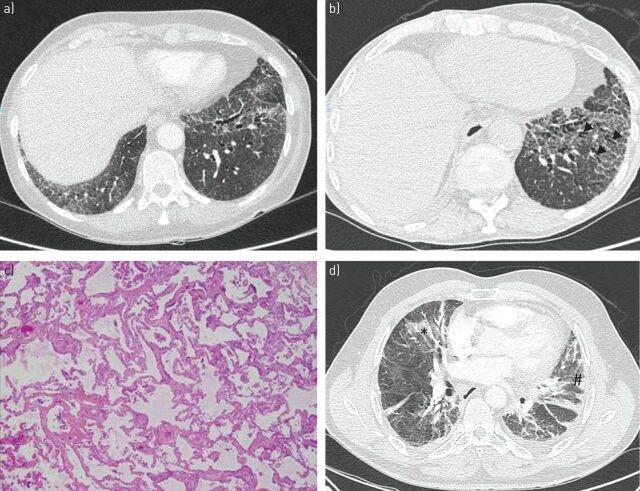

In 9-20% of cases, Sjögren's syndrome is associated with various respiratory symptoms. The most typical manifestations are chronic interstitial lung disease (ILD) and tracheobronchial disease. The most common manifestation of ILD is nonspecific interstitial pneumonia in its fibrosing variant. Other types of ILD, such as organising pneumonia, usual interstitial pneumonia and lymphocytic interstitial pneumonitis, are rare. Their radiological presentation is less distinctive, and definitive diagnosis may require the use of transbronchial or surgical lung biopsy. Corticosteroid therapy is the mainstay of ILD treatment in Sjögren's syndrome, but the use of other immunosuppressive drugs needs to be determined. ILD is a significant cause of death in Sjögren's syndrome. Tracheobronchial disease is common in Sjögren's syndrome, characterised by diffuse lymphocytic infiltration of the airway. It is sometimes responsible for a crippling chronic cough. It can also present in the form of bronchial hyperresponsiveness, bronchiectasis, bronchiolitis or recurrent respiratory infections. The management of these manifestations may require treatment for dryness and/or inflammation of the airways. Airway disease has little effect on respiratory function and is rarely the cause of death in Sjögren's syndrome patients. Rare respiratory complications such as amyloidosis, lymphoma or pulmonary hypertension should not be disregarded in Sjögren's syndrome patients.

在9%至20%的病例中,干燥综合征与多种呼吸道症状相关。最典型的表现是慢性间质性肺疾病(ILD)和气管支气管疾病。ILD最常见的表现是纤维化型非特异性间质性肺炎。其他类型的ILD,如机化性肺炎、寻常型间质性肺炎和淋巴细胞间质性肺炎则较为罕见。它们的影像学表现不太具有特征性,明确诊断可能需要进行经支气管或外科肺活检。糖皮质激素治疗是干燥综合征中ILD治疗的主要手段,但其他免疫抑制药物的使用需要确定。ILD是干燥综合征患者死亡的重要原因。气管支气管疾病在干燥综合征中很常见,其特征是气道弥漫性淋巴细胞浸润。它有时会导致严重的慢性咳嗽。它也可能表现为支气管高反应性、支气管扩张、细支气管炎或反复呼吸道感染。这些表现的管理可能需要对气道干燥和/或炎症进行治疗。气道疾病对呼吸功能影响较小,很少是干燥综合征患者死亡的原因。干燥综合征患者不应忽视罕见的呼吸道并发症,如淀粉样变性、淋巴瘤或肺动脉高压。